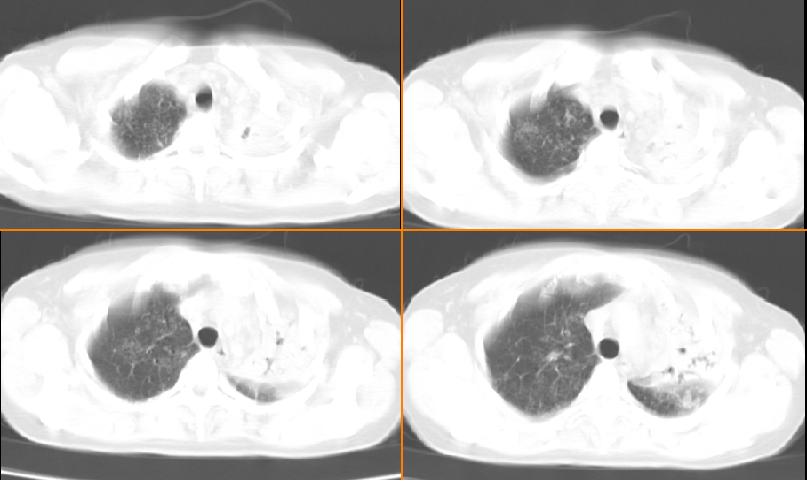

女,33岁,咳嗽5月。

左肺上叶前段致密,内见空气支气管征,相应部位胸膜增厚粘连,双肺上其他肺叶不同程度斑片状播散病灶,结合咳嗽5月的病史,考虑:双肺上叶继发性肺结核。

左肺上叶前段致密,内见空气支气管征,相应部位胸膜增厚粘连,双肺上其他肺叶不同程度斑片状播散病灶,结合咳嗽5月的病史,考虑:双肺上叶继发性肺结核伴左肺上叶肺含气不良。